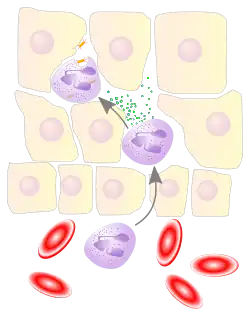

Neutrophils are a type of phagocyte and are normally found in the bloodstream. During the beginning (acute) phase of inflammation, particularly as a result of bacterial infection, environmental exposure,[8] and some cancers,[9][10] neutrophils are one of the first responders of inflammatory cells to migrate toward the site of inflammation. They migrate through the blood vessels and then through interstitial space, following chemical signals such as interleukin-8 (IL-8), C5a, fMLP, leukotriene B4, and hydrogen peroxide (H2O2)[11] in a process called chemotaxis. They are the predominant cells in pus, accounting for its whitish/yellowish appearance.[12]

Neutrophils undergo a process called chemotaxis via amoeboid movement, which allows them to migrate toward sites of infection or inflammation. Cell surface receptors allow neutrophils to detect chemical gradients of molecules such as interleukin-8 (IL-8), interferon gamma (IFN-γ), C3a, C5a, and leukotriene B4, which these cells use to direct the path of their migration.

Being highly motile, neutrophils quickly congregate at a focus of infection, attracted by cytokines expressed by activated endothelium, mast cells, and macrophages. Neutrophils express[33] and release cytokines, which in turn amplify inflammatory reactions by several other cell types.

In addition to recruiting and activating other cells of the immune system, neutrophils play a key role in the front-line defense against invading pathogens, and contain a broad range of proteins.[34] Neutrophils have three methods for directly attacking microorganisms: phagocytosis (ingestion), degranulation (release of soluble anti-microbials), and generation of neutrophil extracellular traps (NETs).[35]

Phagocytosis

Neutrophils are phagocytes, capable of ingesting microorganisms or particles. For targets to be recognized, they must be coated in opsonins – a process known as antibody opsonization.[19] They can internalize and kill many microbes, each phagocytic event resulting in the formation of a phagosome into which reactive oxygen species and hydrolytic enzymes are secreted. The consumption of oxygen during the generation of reactive oxygen species has been termed the "respiratory burst", although unrelated to respiration or energy production.